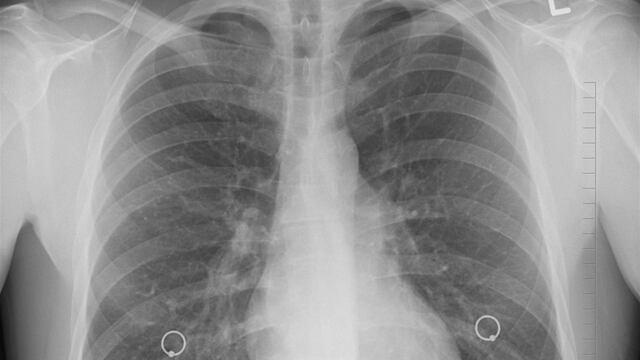

Una mujer residente de Estados Unidos murió tras un trasplante de pulmones infectados con Covid-19 en el Hospital de la Universidad de Michigan. El cirujano que se encargó de la operación también resultó contagiado.

Según los médicos, tanto la donante como la receptora dieron negativo a las pruebas de Covid-19 rutinarias que se recolectan tanto en las vías nasales como en la garganta. No obstante, la mujer que recibió los pulmones murió apenas dos meses después del trasplante.

El caso de la mujer que murió dos meses después de someterse a un trasplante de pulmones infectados con Covid-19 en Estados Unidos sería el primero comprobado de contagio de coronavirus por una intervención de este tipo, aunque las pruebas iniciales indicaron que no existía presencia del virus en los órganos.

La donante fue una mujer que sufrió una lesión cerebral tras un accidente en automóvil, mientras que la receptora tenía una enfermedad pulmonar obstructiva crónica en el Hospital Universitario de Ann Abor. Tres días después del trasplante, la víctima comenzó a sufrir de fiebre, presión arterial baja y respiración dificultosa.

Shock séptico y problemas de función cardiaca fueron parte de las otras complicaciones que desarrolló la paciente, lo que desató que los especialistas aplicaran una prueba para detectar Covid-19, que resultó positiva. Este último examen se realizó a muestras de líquido pulmonar profundo.